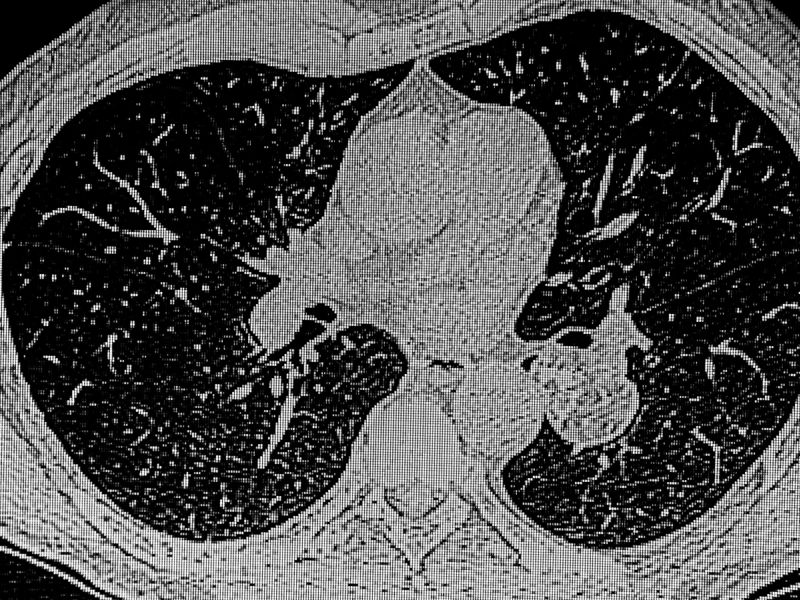

رئة الفشار Popcorn Lung أو ما يسمى التهاب القصيبات المسدودة، يعتبر نوع غير شائع ونادر جدًا من أمراض الرئة، ويصيب أصغر مجاري الهواء في الرئتين نتيجة استنشاق مواد سامة أو عدوى. الأشخاص أكثر عرضة للإصابة بمرض رئة الفشار هم الذين يستخدمون السجائر الإلكترونية بشكل مفرط، إذ تحتوي سوائل السجائر الإلكترونية على مادة الدياستيل المسببة لرئة الفشار، ويحتاج مريض رئة الفشار لرعاية مدى الحياة ويجب تجنب التلوث تماماً، مما تسبب لمرض ...